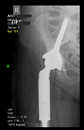

The guiding wire was inserted and controlled with fluoroscopy flashes (Figure 4). The drilling and reaming were carried out in accordance with the recommendations:

Figure 4.

The biocompatible aiming device after insertion of the guiding wire.

The direction of the cup stem was determined by the guide wire. The aiming device was needed to introduce this wire. After removing the aiming device, the next step was the drilling. Since a cannulated drill bit was used, the previously installed wire could guide the process. A self-positioning reaming tool was then used in the drilled channel. In the prepared cavity, the cup was fitted perfectly. Of the two stemmed cups available to us, the McMinn cup (Waldemar Link, Hamburg, Germany) had the simpler geometry and was therefore chosen. The stemmed cup was inserted according to the manufacturer’s recommendation. In the presence of a significant bone defect, a synthetic bone graft may be impacted for substitution.

The criterion of a successful revision is to make the hip joint load-bearing again. Using our technique, with proper design, sizing, and insertion, sufficient primary stability can be achieved.